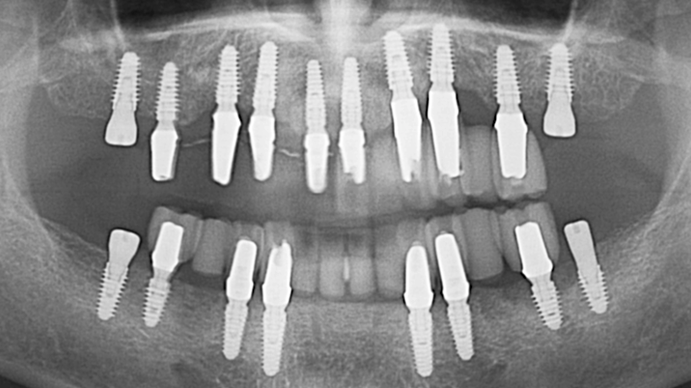

Dr. Sang Tack Lee, edentulous, digital full mouth prosthetics, digital guided surgery, #11, #13, #14, #16, #17, #21, #23, #24, #26, #27, #33, #34, #36, #37, #43, #44, #46, #47, guided surgery, flapless, AnyRidge, R2GATE, Mega ISQ, MEG Torq, MEG Engine, R2GATE Full surgical kit